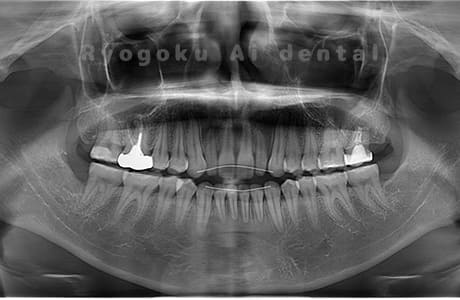

Case03

- 原因

- 上顎、下顎の親知らず

- 治療内容

- 上下4本の親知らずを抜歯したケースです。

<リスク・副作用>

手術後は痛み、腫れ、痺れなどの副作用が生じる場合があります。